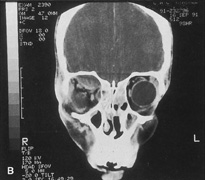

The other important consideration in planning orbitotomy is the position of the tumor within the orbit. Lesions generally may be categorized as either anterior (superficial) or posterior (deep). They can be further categorized by their relationship to the optic nerve (medial, lateral, superior, or inferior to the optic nerve). It may be helpful to further classify the location of lesions relative to adjacent anatomic structures in the orbit. Many surgeons prefer to conceptualize orbital pathologic processes as being located within one or more of seven “surgical spaces” within or around the orbit (Fig. 5). These spaces include:

Fig. 5. Axial drawing of anatomic spaces of the orbit. (1, intraconal space; 2, extraocular muscles; 3, peripheral surgical space; 4, subperiosteal space; 5, preaponeurotic space; 6, Tenon's space; 7, periorbital tissues.)

1. Central surgical space (intraconal space)

2. Extraocular muscles

3. Peripheral surgical space (extraconal space)

4. Subperiosteal space

5. Preaponeurotic space

6. Tenon's space

7. Periorbital tissues

The central surgical space is bounded by the intermuscular septum, which connects the four rectus muscles in the coronal plane. This space also is described as the retrobulbar or intraconal space, and it contains the optic nerve, intraconal fat, and various vascular and neural structures. Primary orbital tumors such as cavernous hemangiomas or optic nerve meningiomas originate in the central surgical space.

Many orbital processes involve the extraocular muscles, primarily or secondarily, making it useful to classify the extraocular muscles as residing in their own separate surgical “space.” Conditions affecting the extraocular muscles include thyroid orbitopathy, myositis, and a variety of neoplastic conditions.

The peripheral surgical space, also known as the extraconal space, lies outside the intermuscular septum but within the periorbita. This space contains a scant amount of orbital fat, the superior oblique muscle and trochlea, inferior oblique muscle, and lacrimal gland. Other important nerves and vessels extend into the space, such as the superior ophthalmic vein. A variety of pathologic processes may encroach on the peripheral surgical space.

The subperiosteal space is a potential space lying between the orbital bones and periorbita. The periorbita may provide a barrier to extension of neoplastic and infectious processes originating in the adjacent sinuses or intracranial cavity. Frequently, the subperiosteal space may fill with blood after orbital fracture or infection when associated with a paranasal sinusitis.

The preaponeurotic space is actually an anterior extension of the extraconal space. Because this space is superficial and readily accessible, sometimes it is referred to as its own orbital compartment. Frequently, neoplasms affecting the lacrimal gland, such as lymphoma, extend forward into the preaponeurotic space.

Tenon's space is a potential space between the sclera and Tenon's capsule. Tumors originating in the eye, such as choroidal melanoma, may extend into Tenon's space.

Secondary orbital tumors may arise from periorbital tissues and secondarily invade the orbit. Cutaneous malignancies arising in the eyelid or facial skin may extend posteriorly through the orbital septum, whereas nasal and paranasal sinus tumors may grow through the orbital bones into or through the subperiosteal space. Tumors arising within the cranial cavity, such as sphenoid wing meningiomas, also may affect the orbit secondarily.